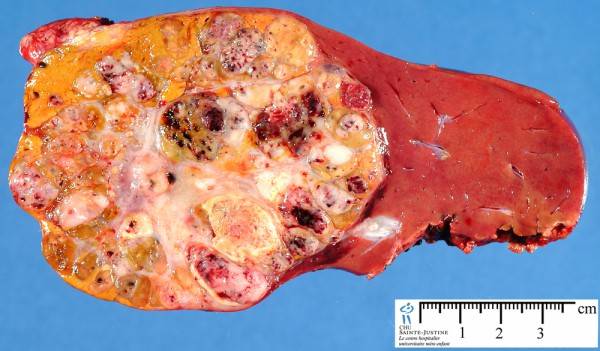

Развивающаяся чаще всего в тканях правой доли печени, гепатобластома представляет собой плотное бескапсульное новообразование (оно может быть как одиночным, так и множественным) желто-белой окраски, напоминающее узел и способное вырабатывать желчь.

Свободно прорастающая в ткани пораженного органа, гепатобластома отличается ярко выраженным дольчатым строением и наличием очагов некроза и кровоизлияний.

На фото показана гепатобластома печени